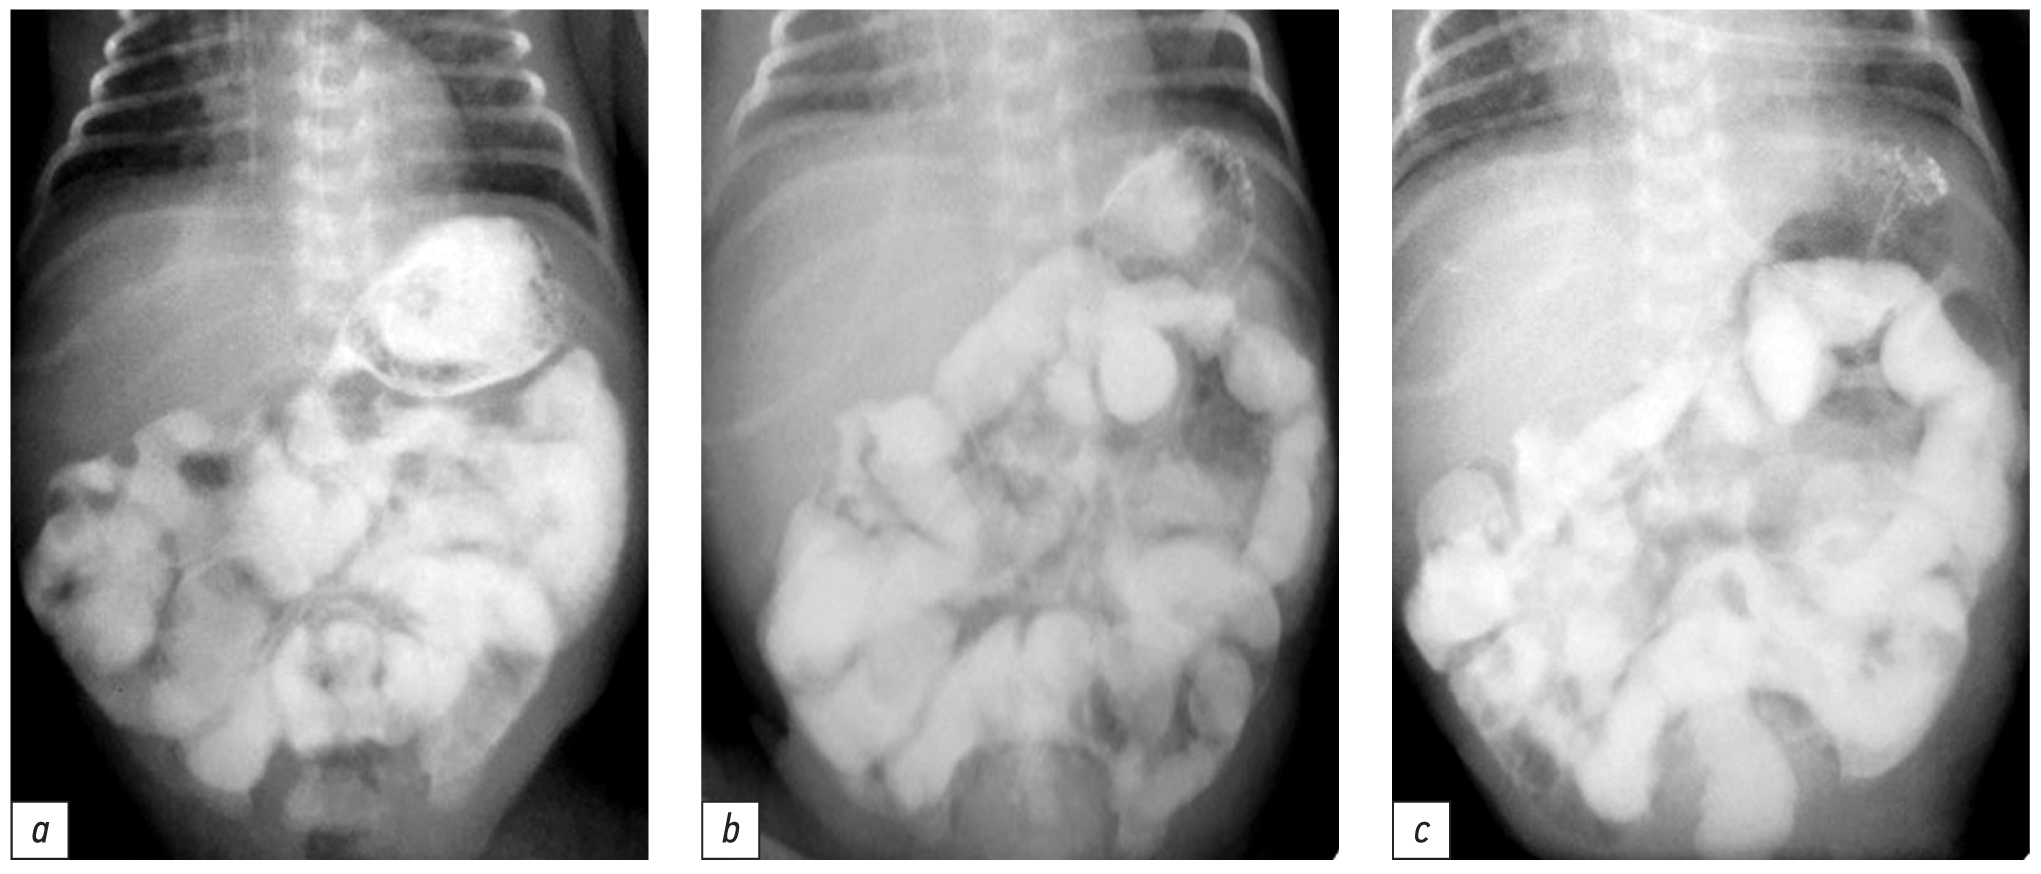

Послеоперационное лечение включало респираторную, инотропную поддержку, анальгезию, инфузионную, антибактериальную терапию. На 5-е сутки после операции в связи со стойкими клиническими признаками пареза кишечника для исключения ранней спаечной кишечной непроходимости проведено пероральное контрастирование желудочно-кишечного тракта после введения водорастворимого контраста. На рентгенограмме через 1, 3, 6 ч после введения контраста наблюдалось замедление времени транзита по кишечнику, признаков непроходимости не отмечалось (рис. 3).

Рис. 3. Пассаж контраста по кишечнику через 1 (a), 3 (b), 6 (c) ч после введения (данных за непроходимость кишечника нет).

Fig. 3. Passage of the contrast through the intestines 1 (a), 3 (b), 6 (c) hours after contrast administration (no evidence of intestinal obstruction).